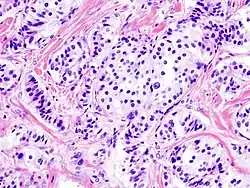

Гистологическая картина

- Патогистология

Панкреатическая инсулинома Окраска инсулиномы Chromogranin A - Histopathology of pancreatic endocrine tumor (insulinoma). Insulin immunostain.